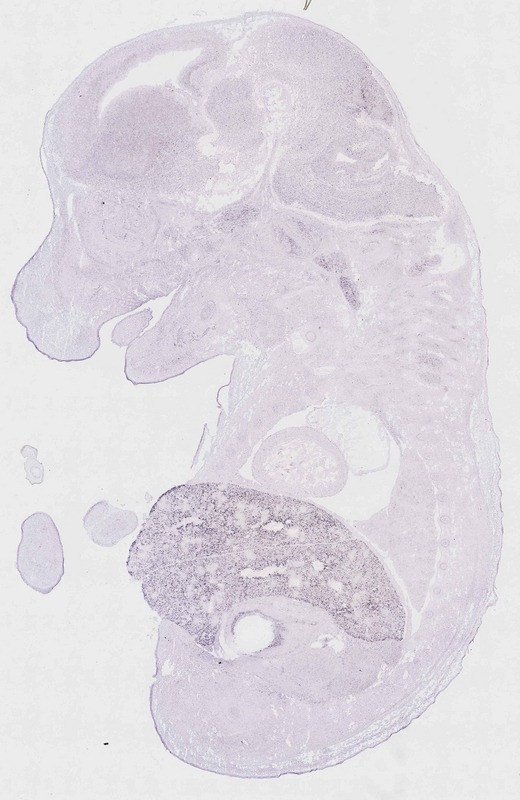

Reference: J:153498 Diez-Roux G, et al., A high-resolution anatomical atlas of the transcriptome in the mouse embryo. PLoS Biol. 2011;9(1):e1000582

Gene symbol: Cyp2d9

Gene name: cytochrome P450, family 2, subfamily d, polypeptide 9

Specimen euxassay_001576_01: embryonic day 14.5 (more )

TS23: liver lobe Strong Single cells euxassay_001576_01